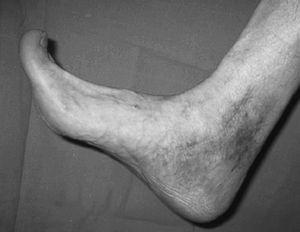

Respecto a las luxaciones del astrágalo, se han encontrado 7 casos de las cuales 5 (71,4%) de ellas eran luxaciones mediales --el pié se desplaza hacia adentro con respecto al astrágalo-- (figs. 13 y 14). La luxación medial es la más frecuentes --el 72% del total según DeLee y Curtis30 y Zimmer y Johnson31, y el 85% para Motley et al6--, seguidas de las laterales (de peor pronóstico) y mas infrecuentes las anteroposteriores.

Fig. 13. --Enucleación del astrágalo. Reducción, desbridamiento y estabilización temporal con agujas K.

Fig. 13. --Enucleation of the astragalus. Reduction, debridement and temporary stabilisation with Kirschner needles.

Fig. 14. --A) Radiografía al sexto mes: osteoporosis. B) Radiografía a los 18 meses: artrosis tibioastragalina.

Fig. 14. --a. Radiography at 6 months. b. Radiography at 18 months: tibio-astragalar arthrosis.